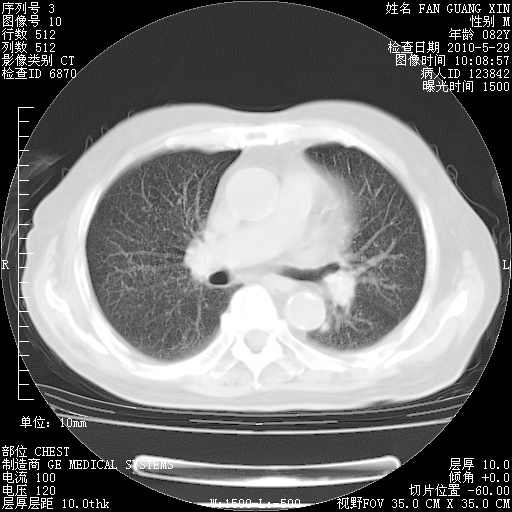

再治疗10天后的肺部CT

从白细胞总数和中性比例看好像合并感染。肺部纹理好像比上次多,支气管炎?其他感染?

阅读此次胸部CT,肺间质渗出性改变较入院时有吸收。目前从体温、白细胞、中性分叶明显增高,肯定存在细菌感染(发生医院感染哦,若无消化道及泌尿系统等感染的依据,肺部感染可能大)。若你院头孢哌酮舒巴坦钠耐药率较高,同意你的方案,若48小时体温仍高,可考虑使用碳青霉稀类抗菌药物,同时可予超声雾化、注意滴数时加大液体量。白蛋白33.30g/L较低哦,需加强营养等支持治疗。